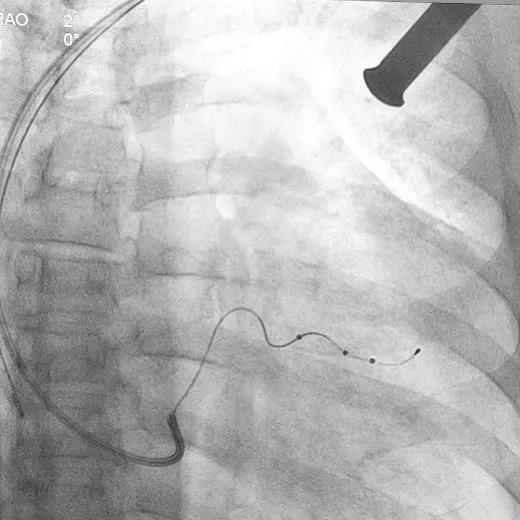

术中影像

(△ 术中)

(△ 使用李氏造影导管寻找冠状窦)

(△ 冠状静脉造影)

(△ 术后,植入电极造影)